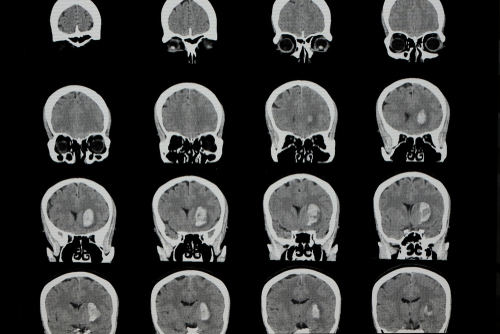

Researchers have developed a system using Artificial Intelligence (AI) to quickly diagnose and classify brain haemorrhages and to provide the basis of its decisions from relatively small image datasets.

To train the system, the research team began with 904 head CT scans, each consisting of around 40 individual images that were labelled by a team of five neuroradiologists as to whether they depicted one of the five haemorrhage subtypes, based on the location within the brain, or no haemorrhage.

To improve the accuracy of this deep-learning system, the team built in steps mimicking the way radiologists analyse images, suggested the study published in the journal Nature Biomedical Engineering. Once the model system was created, the team tested it on two separate sets of CT scans -- a retrospective set taken before the system was developed, consisting of 100 scans with and 100 without intracranial haemorrhage, and a prospective set of 79 scans with and 117 without haemorrhage, taken after the model was created.

In its analysis of the retrospective set, the model system was as accurate in detecting and classifying intracranial haemorrhages as the radiologists that had reviewed the scans had been, the team said. In its analysis of the prospective set, it proved to be even better than non-expert human readers, they added.